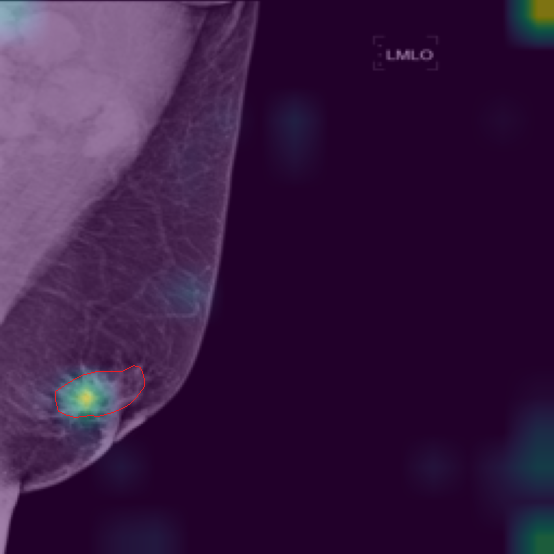

5.9 ViKL Provides Evidence for Clinical Decision

In our earlier sections, we discussed how ViKL enhances the image branch’s capability for detailed feature extraction by using text and manifestations that describe localized lumps. To directly observe this enhanced feature extraction ability, we utilize the class activation map (CAM) [62], a common tool for visualizing neural network activations. Specifically, we employ Grad-CAM [63] to generate activation maps from the third layer of the ResNet50 model, which has been fine-tuned using ViKL on the MKVL dataset. Additionally, for accurate visualization and comparison, we include markings of lumps as annotated by professional radiologists. The results of this visualization are showcased in Fig. 6. These visualizations demonstrate ViKL’s effective localization of small lesions, highlighting its refined ability to capture minute features in medical imaging.